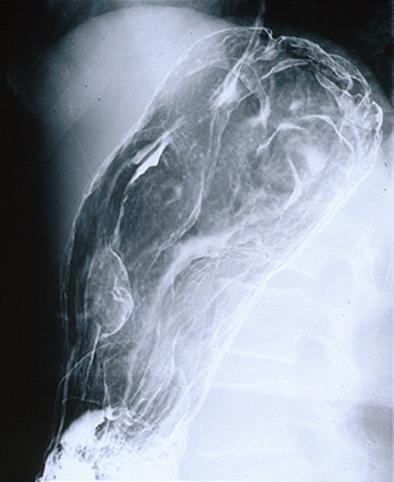

clasificación del pacienteLinfoma Maligno/Linfoma Maligno tipo MLP

parte(separada por órganos)estómago(región)/mas de dos

método de exámenRayos X

diámetro mayor del tumor30 - 34

múltiples tumores(en un mismo órgano)presente(simultáneo-metacrónico)

múltiples tumores(en varios órganos)presente(simultáneo-metacrónico)